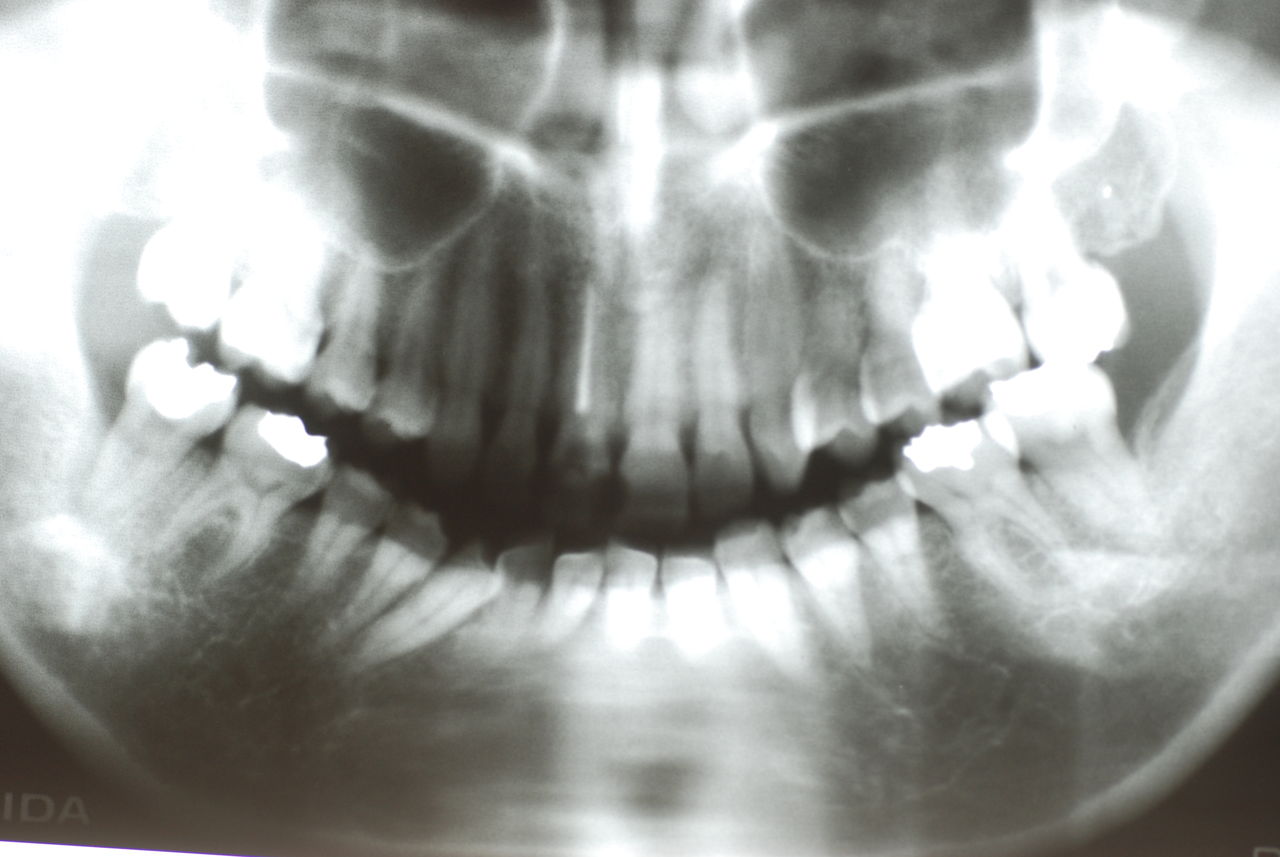

flabby gumと言いまして、骨が溶けてぶよぶよになった歯茎が残るとても入れ歯が吸着したり安定的に食べ物が噛めるような状態でないのです。(歯周病で骨が溶けたとか合わない入れ歯を入れているとなりやすい。)

そしてその部分が擦れて痛む為食事もできないのです。それ以上に驚いたのは、歯を磨いたり歯周病の治療の話を聞いたことがないという事実です。

下の歯は数本存在しますが、全て虫歯と歯周病に犯されていました。

触るとぶよぶよしていて強く押すと痛みがあります。

食べカスまみれで歯周病に罹患しています。

殆ど出っ張りがない上顎の部分です。